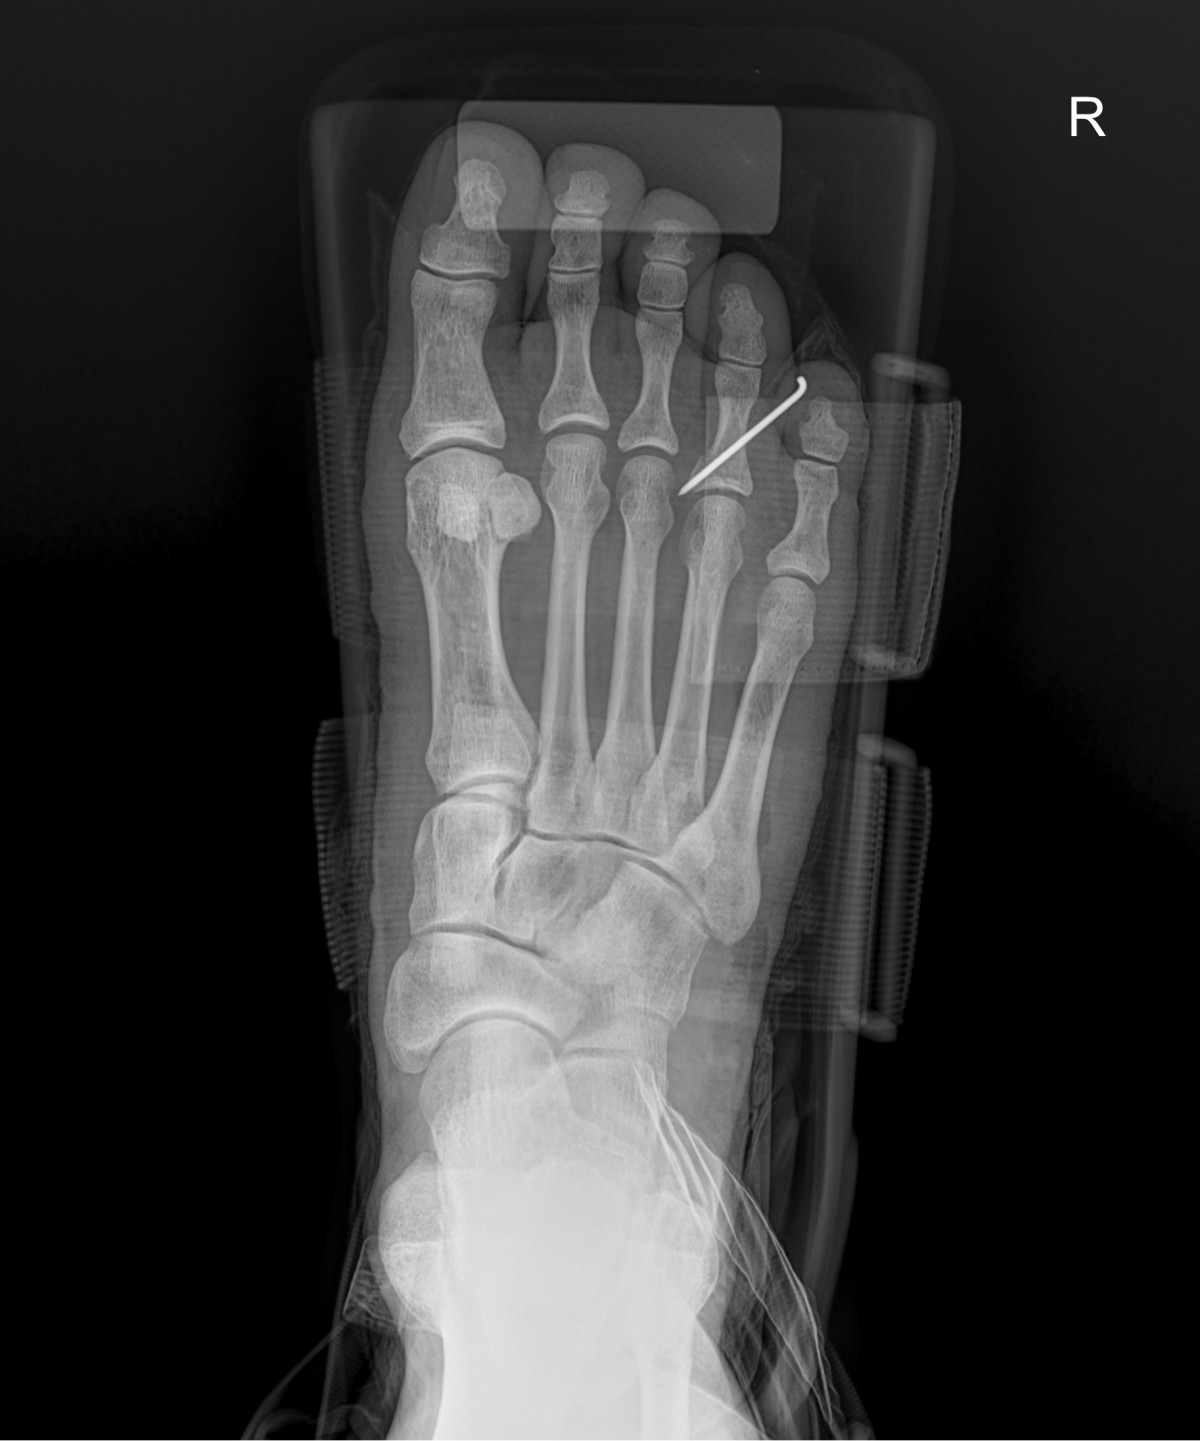

정지영원장님 발가락 골절 수술 윤주O 환자

dae765e4d9ac96aee867c9d6292d8784_1758008244_9308.jpg